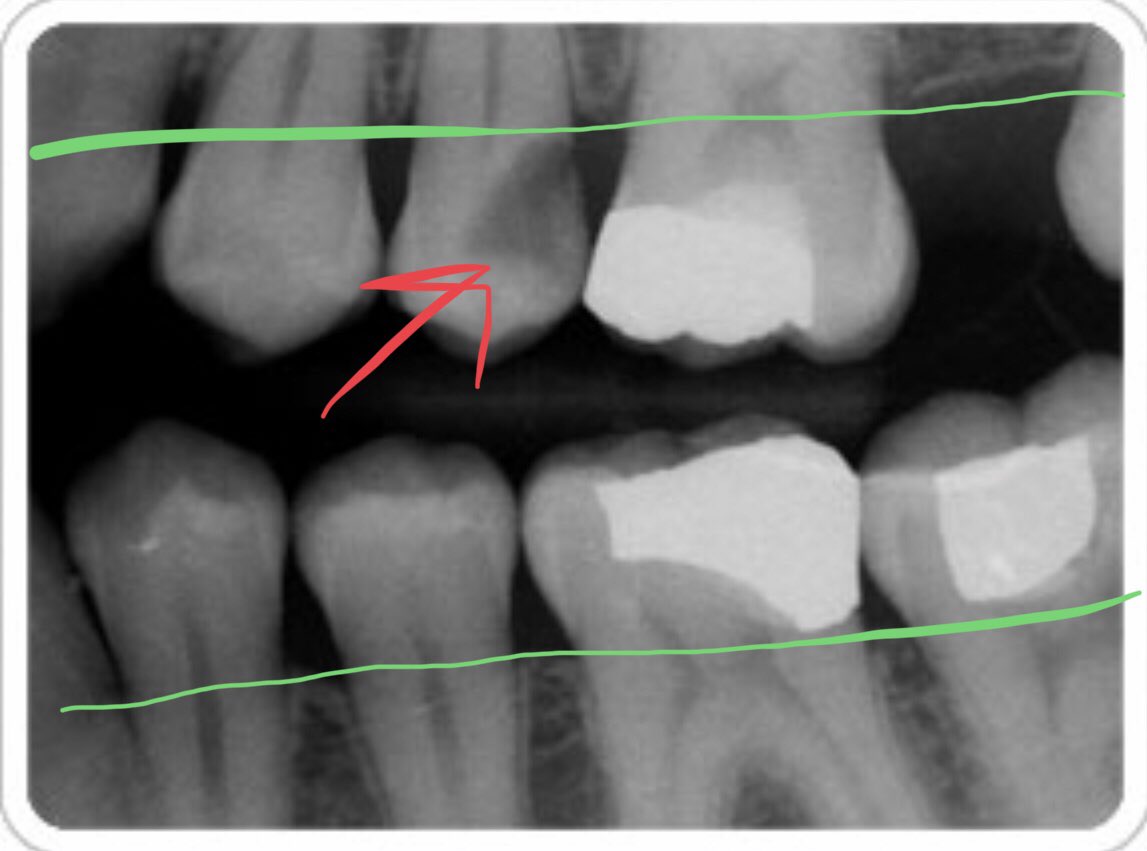

اما النوع الثاني فيسمى اشعة العضة المجنحة Bite wing ويطلب من المريض العض على اسنانه خلالها وتغطي سنين او ثلاثه من #الاسنان الخلفيه (أضراس والضواحك) وهي ادق من اشعة PA السابقة لان طريقة اخذها تحتمل انحراف اقل ودقة اعلى

وهي شبيهة بالنوع الاول (الاشعة الصغيره) لكن تستخدم في التالي:

-إيضاح التسوس بين الاسنان

-علاقة وبعد التسوس عن عظم السن

-مستوى العظم بين وخلال السن لذلك تخدم أخصائي اللثة كثيرا

نلاحظ في الصورة انها أوضحت علاقة التسوس (احمر ) بمستوى العظم (اخضر)